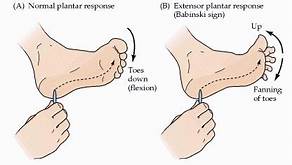

5. Babinski reflex / Plantar reflex